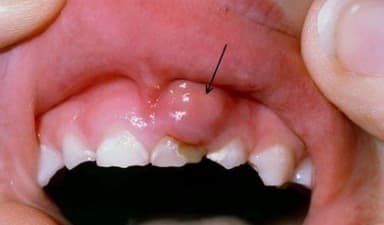

3.1 Điều trị cao răng

Thực hiện lấy cao răng giúp ngăn ngừa các bệnh lý răng miệng (có thể điều trị bệnh lý nếu phát hiện thấy). Việc lấy đi lớp cao răng bằng các dụng cụ nha khoa chuyên dụng sẽ giúp lấy được những mảng vôi cứng trên răng và hoàn toàn không gây ảnh hưởng nếu bạn thực hiện tại các cơ sở nha khoa uy tín với bác sĩ tay nghề chuyên môn cao.